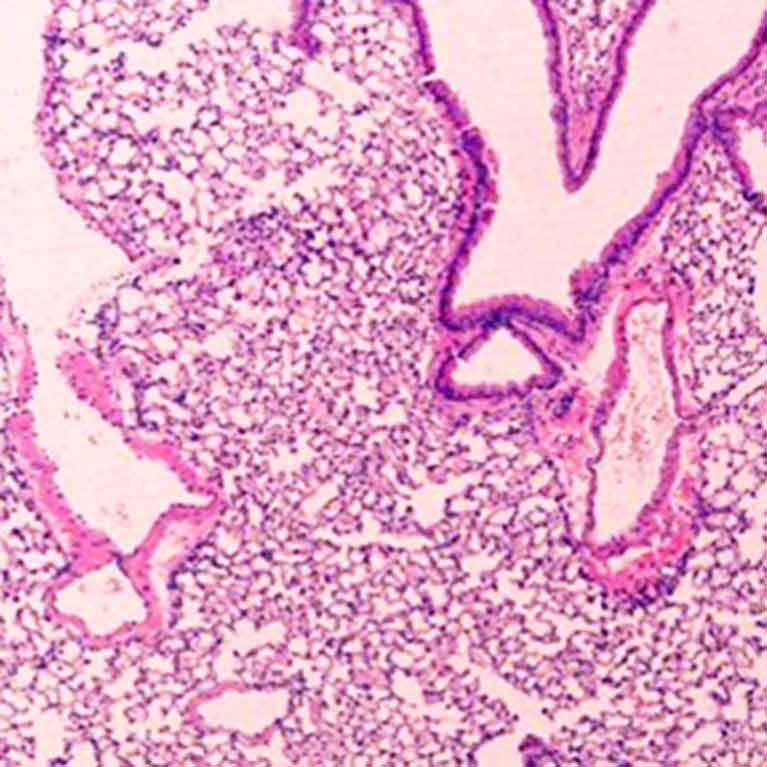

To learn how to strengthen or correct the immune system, Ye Zheng focuses on a specialized set of immune cells called regulatory T (Treg) cells. Tregs control the immune response, telling the more aggressive immune cells when to stop their frenzied attack. Abnormal Treg cell function has been linked to multiple autoimmune diseases and tumors. In particular, a key molecular component of these cells, a protein called Foxp3, is often responsible for deficient Tregs. Zheng is making advances in understanding the genes that control Foxp3—as well as genes that Foxp3 controls—to ultimately lead to ways to manage Treg cell function. Since manipulations of Treg cells can either weaken or strengthen the immune response, his findings can potentially open new avenues in the treatment of autoimmune diseases, improve organ transplant survival and uncover new cancer targets.